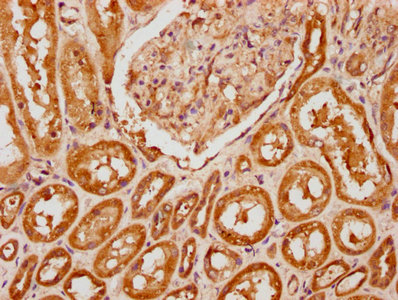

IHC image of PACO60925 diluted at 1:200 and staining in paraffin-embedded human kidney tissue performed on a Leica BondTM system. After dewaxing and hydration, antigen retrieval was mediated by high pressure in a citrate buffer (pH 6.0). Section was blocked with 10% normal goat serum 30min at RT. Then primary antibody (1% BSA) was incubated at 4°C overnight. The primary is detected by a biotinylated secondary antibody and visualized using an HRP conjugated SP system.